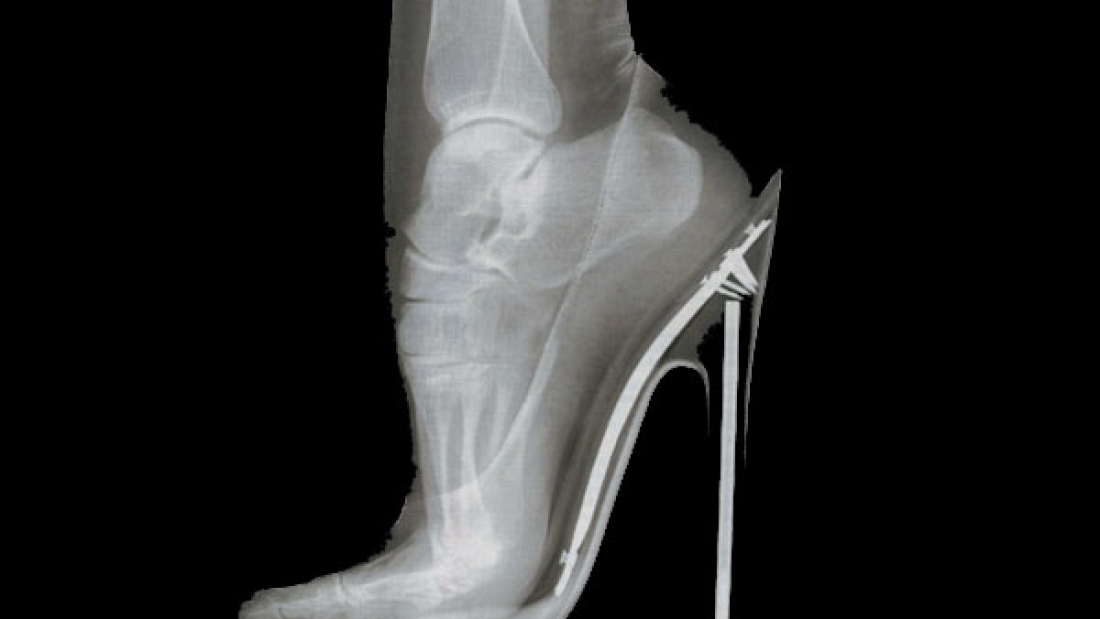

Andar con tacones, que problemas puede causar y como evitarlo

Entre otras funciones el calzado constituye un elemento de protección del pie, dan sensación de confort a la par que dan estabilidad y amortiguación del pie. Sin embargo según el tipo y la calidad de los mismos puede convertirse en uno de los principales enemigos de la salud de nuestro. Molestias, dolor, hinchazones y hasta deformaciones en los huesos (juanetes, dedos martillo …)

El uso de tacones cada vez es más habitual en el día a día de las mujeres, andar con tacones muy altos hace que el cuerpo se incline hacia adelante, los dedos deben soportar mas peso y eso generará molestias.

Los especialistas advierten que usar tacones de manera habitual puede causar daños irreversibles.

Los podólogos aconsejan que en caso de usar tacones, estos sean los más bajos posibles, intentando que no excedan de los 4 o 5 cm y con la horma lo más ancha posible. Además se debe evitar el uso diario para evitar que acabe afectando a la salud de tu pie.

Según, Carlos San Martín, secretario de la Escuela de Podología de la Universidad Complutense de Madrid, «las molestias que sufren las mujeres en los pies sí guardan relación en muchas ocasiones con el tacón alto. Un buen tacón debe tener como máximo tres centímetros y ha de ser ancho, aunque el mejor de todos es el que posee esta altura, aunque con forma de cuña».

No es menos cierto que los podologos no consideran un riesgo el uso de tacones de manera puntual, el problema suele venir con el abuso y uso regular de los mismos.

Los efectos nocivos del uso de tacón alto pueden ser varios,y mucho más aún si se parte de una patología previa en la zona del antepié, una fractura previa de metatarsianos o problemas en los dedos como dedos en garra o en martillo, que hacen aumentar más la presión sobre esta zona.